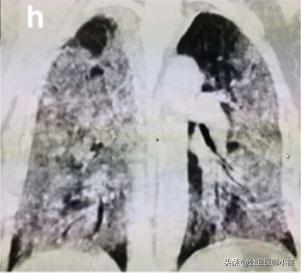

恶化

如果治疗不及时,或者免疫力无法抵御病毒,则很可能威胁生命,发展为白肺。

白肺,肺部恶化

当然白肺在仅仅发生在极少数弥漫性肺部损伤且涉及多个肺叶的危重型患者。

在此阶段,患者肺通气功能严重受损需要持续性吸氧,甚至需要进行体外膜氧合(ECMO)俗称人工肺。